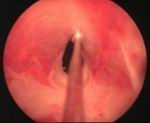

• A look into the urethra by a special thin telescope will be needed to assess the stricture.

In this procedure, a thin telescope is passed into the urethra to see exactly where the stricture is. This is done during a general anaesthetic. A tiny knife is then passed down the telescope to cut along the stricture. This widens the narrowed stricture. You will get some relief of symptoms from this procedure. About one case in three is cured for good. However, like dilation, the stricture may re-form and the procedure may have to be repeated from time to time in some cases.